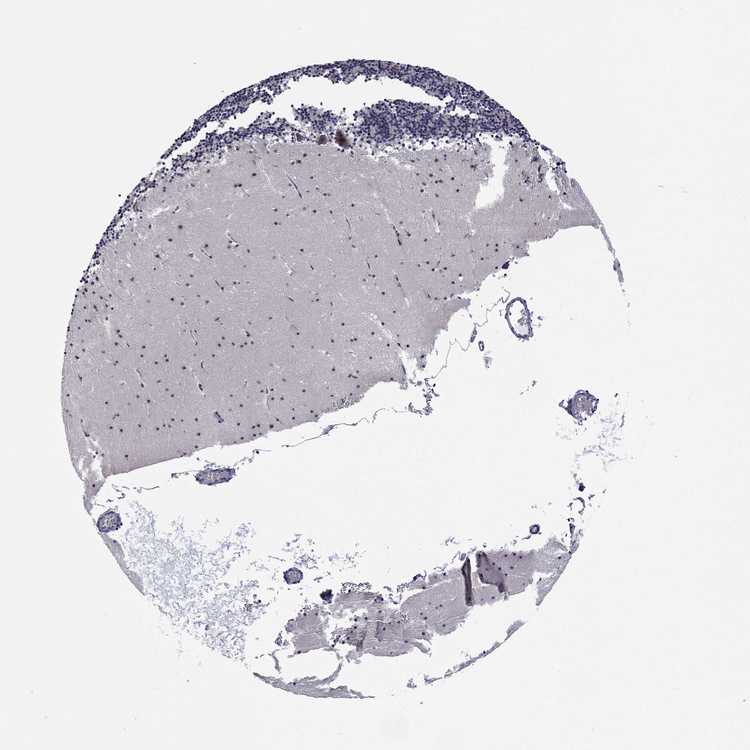

CEREBELLUM - Antibody stainingi

Antibody staining in the annotated cell types in the current human tissue is reported as not detected, low, medium, or high, based on conventional immunohistochemistry profiling in selected tissues. This score is based on the combination of the staining intensity and fraction of stained cells.

Each image is clickable and will lead to virtual microscopy that enables deeper exploration of all samples and also displays staining intensity scores, fraction scores and subcellular localization as well as patient and tissue information for each sample.

Antibody HPA071317

Purkinje cells Not detected

Cells in granular layer Low

Cells in molecular layer Not detected